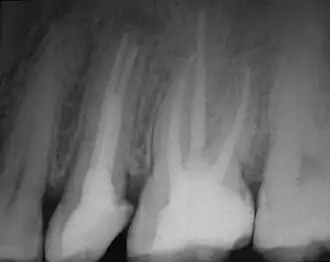

Предложенная Vertucci классификация относится к каждому отдельному корню, поэтому в различных корнях многокорневых зубов могут встречаются любые комбинации типов. Следует подчеркнуть, что данная классификация даёт весьма грубую и приблизительную схему возможных вариантов систем корневых каналов. Таким образом, представленные схемы на практике могут отличаться вариабельностью, встречаться в разных комбинациях, создавая весьма сложную топографию системы корневых каналов. Особую настороженность должны вызывать у клиницистов случаи наличия множественных апикальных отверстий, имеющие немаловажное значение в возникновении возможных осложнений после проведения эндодонтического вмешательства[3]. Именно поэтому практикующие врачи-стоматологи перед началом процедуры депульпирования проводят рентгенографическое обследование, позволяющее достоверно определить тип и количество корневых каналов в зубе[2].

- витальная экстирпация — при отсутствии выраженных воспалительных явлений, переходящих в периодонт, удаление сосудисто-нервного пучка и его обтурация проводится под анестезией в одно посещение. В канале оставляют лекарство (для антисептики и снятия воспаления). В процессе лечения необходимо сделать как минимум 2 рентгеновских снимка: первый — до начала лечения (для оценки длины и структуры каналов), а второй — после (для оценки качества пломбирования каналов).